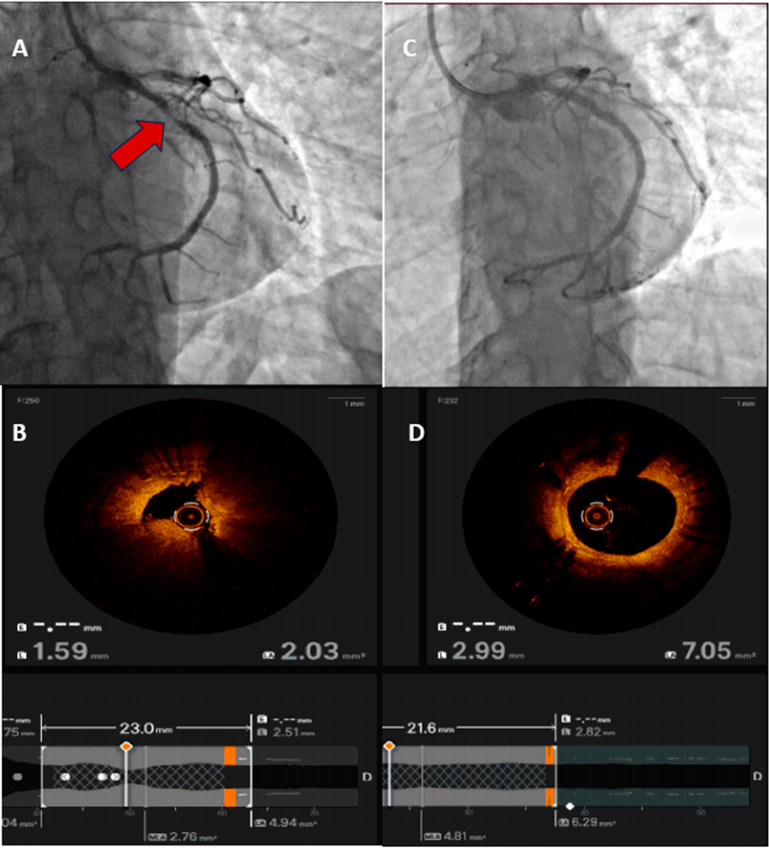

血管内影像(IVUS/OCT)已成为优化ACS患者PCI的核心工具,能改善支架尺寸选择、扩张与贴壁,从而减少不良事件(图1)。一项大型当代荟萃分析证实,与单纯造影引导相比,影像引导的支架置入能显著降低复合不良结局(图2)。在功能学评估方面,FLOWER-MI试验显示,在STEMI患者中,FFR引导的完全血运重建并未优于造影引导。当前实践趋势倾向于:对ACS PCI(尤其是左主干、分叉、钙化等复杂病变)常规使用影像引导;在患者病情稳定后,可选择性使用功能学来辅助非罪犯病变的决策。

图2. OCT引导的ACS介入治疗示例。(A) 冠状动脉造影显示左回旋支近端存在显著狭窄(箭头所示);(B) OCT图像显示斑块破裂及管腔状况;(C) 针对罪犯病变行PCI后的造影结果;(D) OCT显示支架置入后的效果。